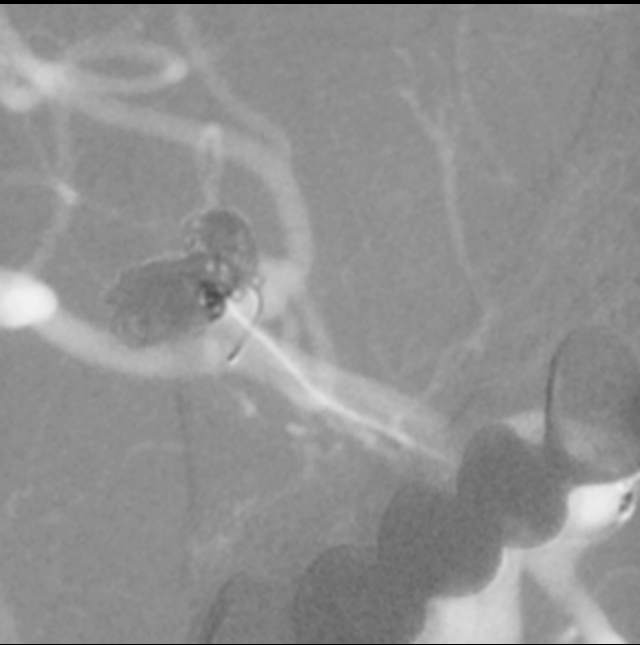

话归正传,下面我们看看如何分兵使用“犄角之势”的策略夹击栓塞“犄角之势”的硬骨头(分叉部绝对宽颈带有俩角的动脉瘤):两个微导管先后到位,两个子囊内的弹簧圈相互依偎,形成“犄角之势”,共同击杀两者之间的大本营(共同的瘤体),最终致密栓塞动脉瘤,消除了动脉瘤再次兴风作浪(再出血)的风险,也最大限度的保全了各个分支血管(粮道)的安全,急性期也没有使用支架,降低了费用,还保障了安全。

栓塞一个复杂动脉瘤,就是进行一场战争。采用“犄角之势”致密单纯栓塞动脉瘤后,指挥者(术者)没有支架内血栓的顾虑,也不担心再出血的侵扰,还有止血药、降压药的保驾护航,可以安心班师回朝了~~~